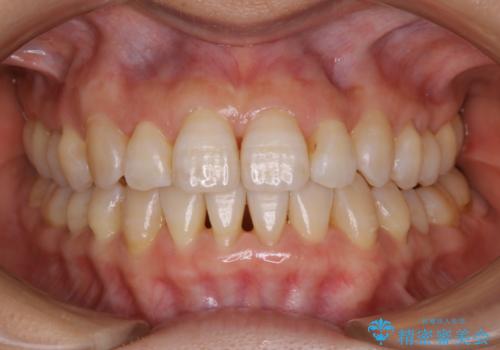

- かみ合わせ、顎のゆがみ、歯の見た目を主訴に来院された患者様です。

上の顎が下の顎に比べて小さく、それによって下の顎の位置をずらすことでしか噛めない状態でした。

また部分的に下の歯が上の歯よりも前に出てきてしまっていて、見た目にも問題がありました。